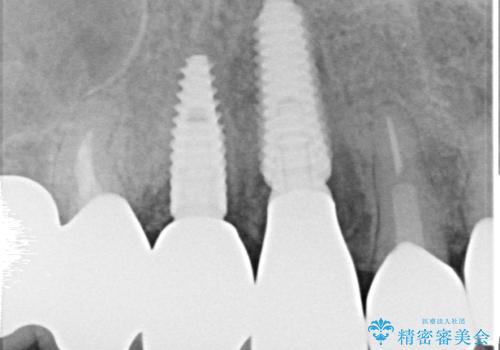

全顎的な治療後に、急遽ニューヨークへ転居されることとなったのですが、治療後から経過観察を行っていた右上犬歯が歯肉縁下に及ぶむし歯のため、クラウンが土台ごと外れてしまったとの連絡がありました。

他の部位にインプラント治療を行っていたことから、こちらの歯に対してもインプラントによる補綴治療を希望されたため、1泊での帰国時に抜歯、インプラント埋入、仮歯の装着を行い、数ヶ月後の帰国時にオールセラミッククラウンの型取りと装着を行う計画としました。

インプラント埋入時は1泊、補綴治療時には3週間ほど日本に滞在していただき、2回の渡航で無事に治療を終えることができました。